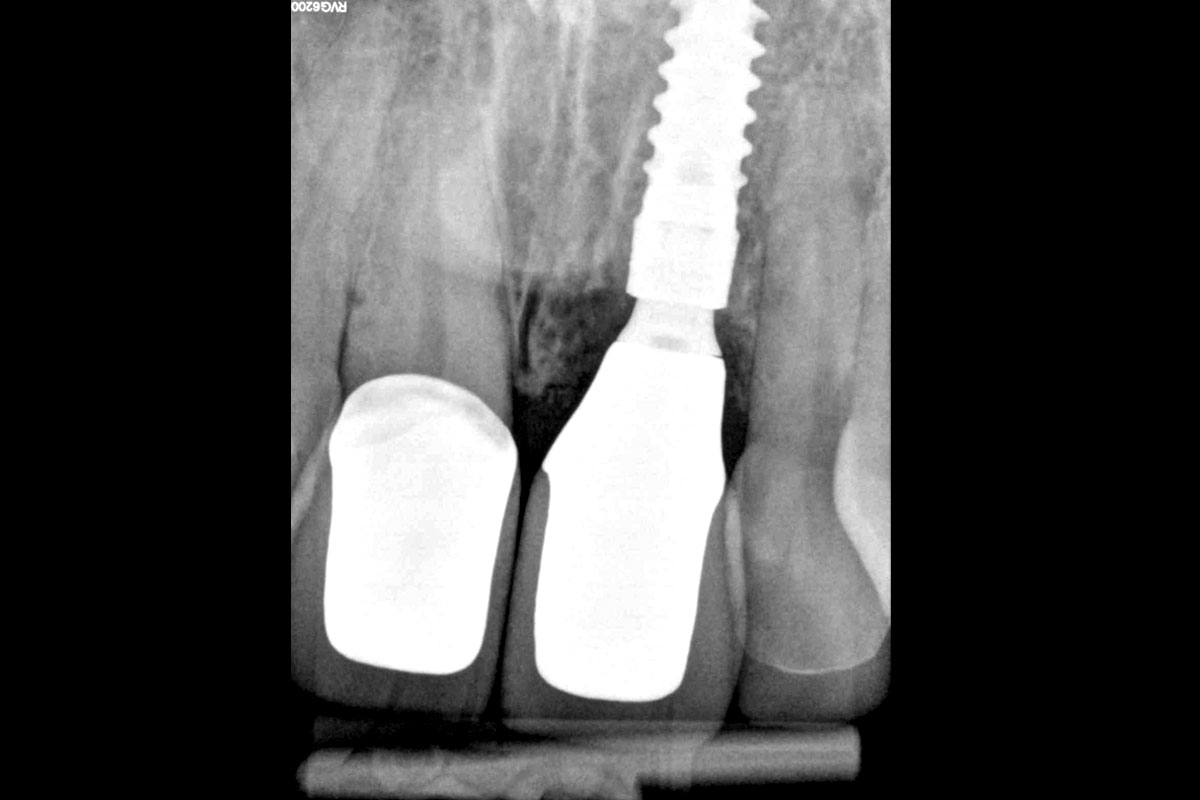

28/30 - Radiological control after surgeryExcellent aesthetic result of buccal augmentation with mucoderm® and maxgraft® after immediate implant placement - 3-years follow-up - Dr. A. Puišys